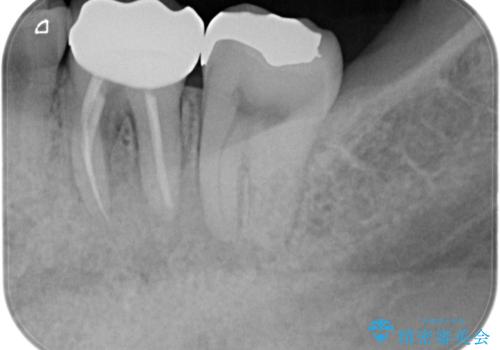

根管治療から被せ物の治療

根管治療を行なったのち、症状改善を認めオールセラミッククラウンにて修復治療を行なっております。

┌7は今回の治療後打診(-)、正常歯髄へ診断のもと経過観察を行なっております。

根管治療後は速やかに歯冠修復が必要です。